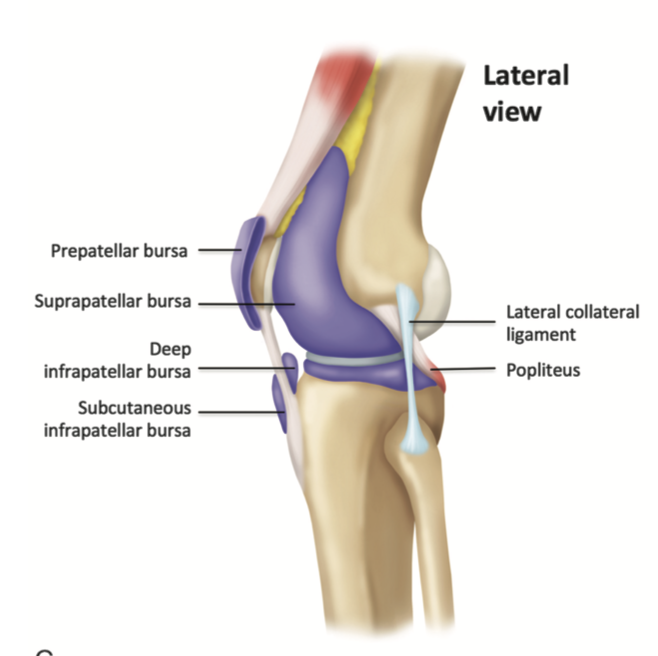

What structure appears as a thin hypoechoic line just beneath the quadriceps femoris tendon?

Suprapatellar bursa.

What is the common site for access to the knee joint?

A

What is located beneath the patellar tendon?

Intracapsular Hoffa’s fat pad.

What does the medial collateral ligament reveal when the ultrasound probe is placed over its long axis?

Superficial layer and the deep meniscofemoral and meniscotibial components.

Going down to Tibia insertion: Pes anserinus complex inserting into the anterolateral aspect of the tibial metaphysis. At this level, the 3 tendons of sartorius, gracilis, and semitendinosus cannot be differentiated from each other.

What is the best position for examining the lateral knee?

Knee internally rotated with 20- to 30-degree flexion.

Where is the lateral collateral ligament best examined?

Over the fibula head with the probe rotating over the femur.